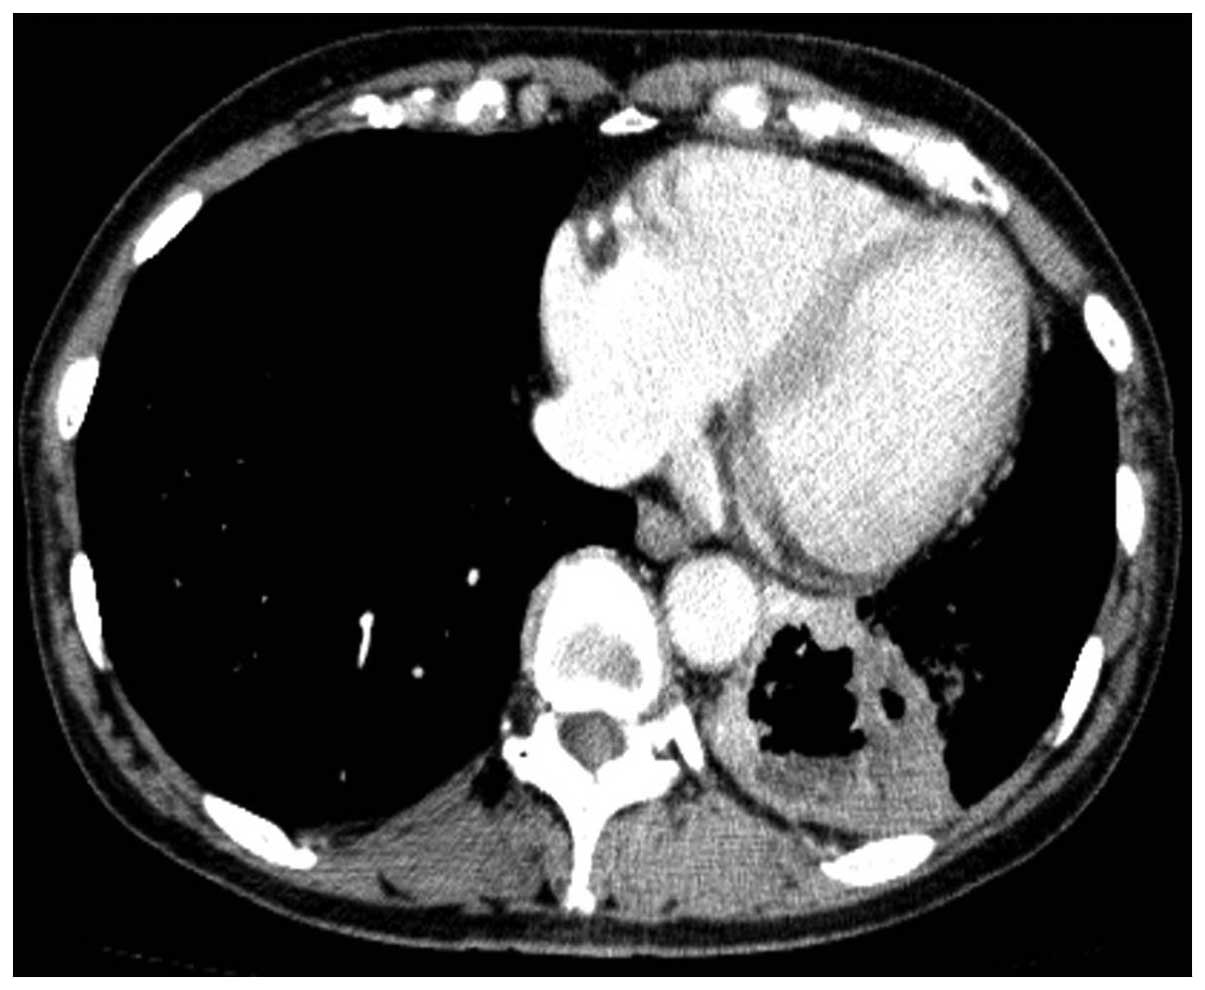

Adenosquamous cell lung cancer successfully treated with gefitinib: A case report

Although adenosquamous cell lung cancer (ASCLC) is included in the non‑small‑cell lung cancers (NSCLCs), the number of currently available studies on the response of this type of cancer to epidermal growth factor receptor‑tyrosine kinase inhibitors (EGFR‑TKIs) is limited. This is the case report of a 66‑year‑old female who was referred to the Mito Medical Center (Mito, Japan) with hemoptysis and the chest computed tomography (CT) scan revealed a large cavitary mass in the lower lobe of the left lung. The patient underwent surgical resection of the lesion and the final pathological diagnosis was ASCLC staged as pT2bN2M0. Notably, an EGFR exon 19 deletion was identified in the adenocarcinomatous as well as the squamous cell carcinomatous components of the tumor. Despite adjuvant chemotherapy, the patient developed small cavitary metastases in the lungs bilaterally. Therefore, treatment with gefitinib was initiated. The chest CT scan revealed substantial regression of the metastatic cavitary tumors in both lungs, with thinning of the walls. The patient remains alive and recurrence‑free 19 months following the initiation of gefitinib therapy. This case demonstrated an optimal clinical response to gefitinib treatment for EGFR mutation‑positive ASCLC, suggesting that gefitinib is a therapeutic option for such a subset of patients with ASCLC.

Figure 4